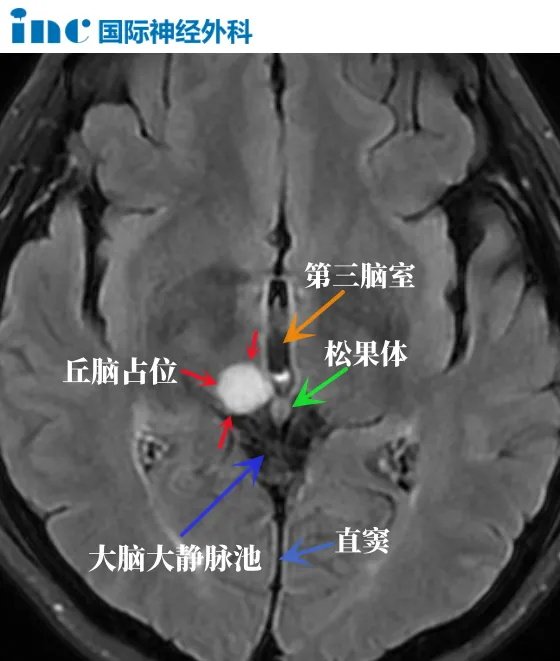

相邻器官重要

丘脑附近重要的邻居有松果体、下丘脑、中脑。

邻居一:松果体

松果体控制着人体的睡眠与觉醒、情绪、智力。